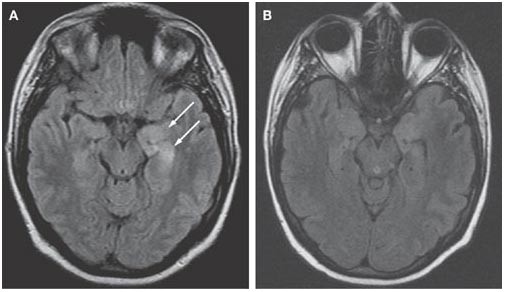

> ⭐ **vCJD**: Pulvinar sign (hyperintensity in posterior thalamus) on MRI is characteristic of variant CJD.